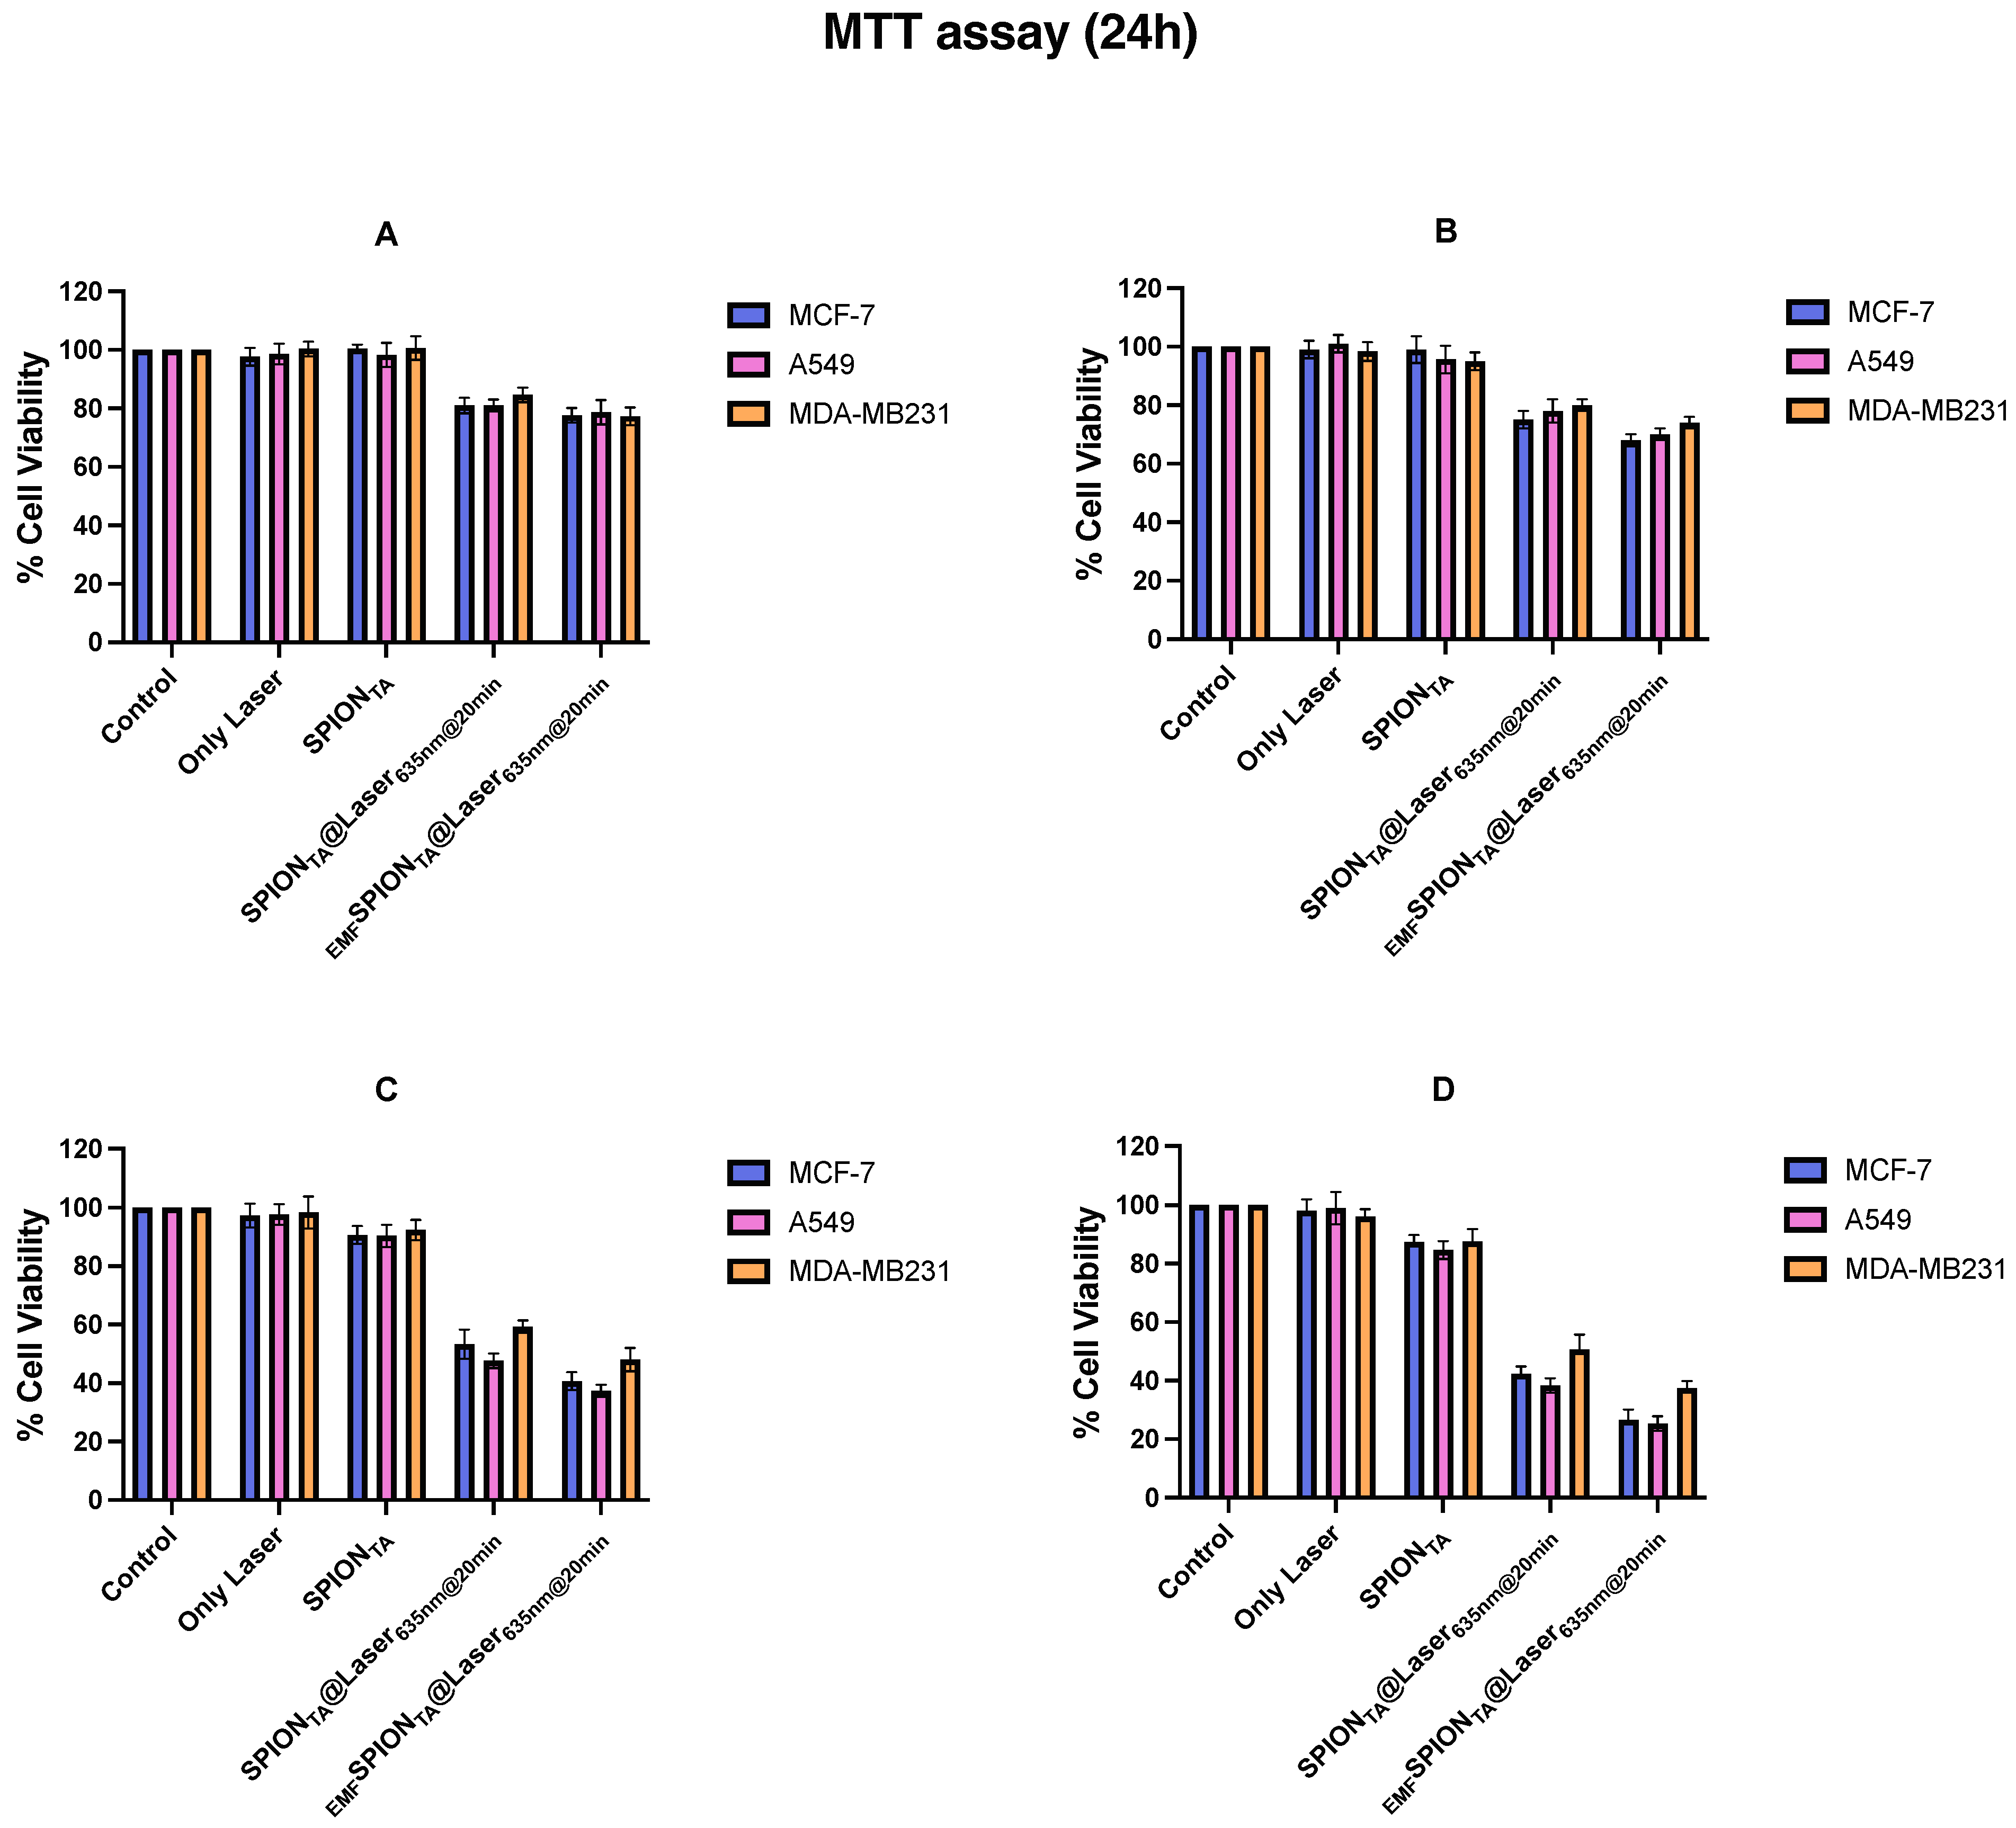

2.8.1. MTT (3-(4,5-Dimethylthiazole-2yl)-2,5-Diphenyltetrazolium Bromide) Assay